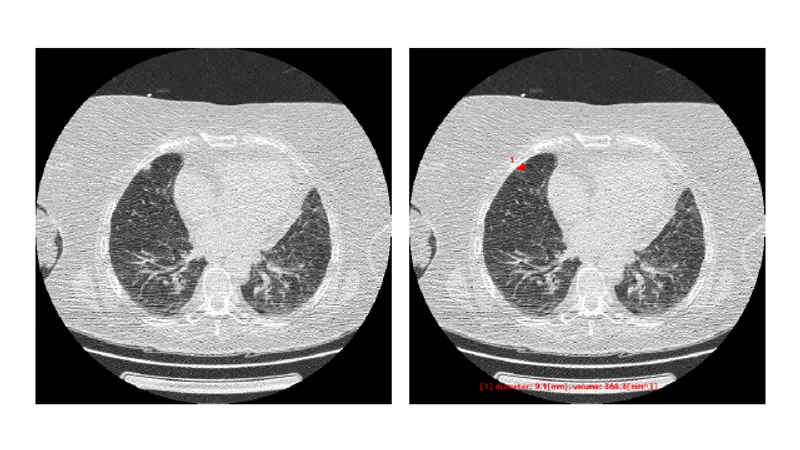

胸部CT画像から「関心領域」を抽出

本サービスは胸部 CT 画像における肺野領域の組織について、関心領域を抽出し体積と最大径を測定します。 また、関心領域の最大径が閾値以上であれば色付けを行います。

本サービスは、医師が設定した基準値に基づいてCT値を元に関心領域を抽出し体積と最大径を自動計測します。 また、関心領域の最大径が医師が設定した閾値以上であれば色付けを行います。